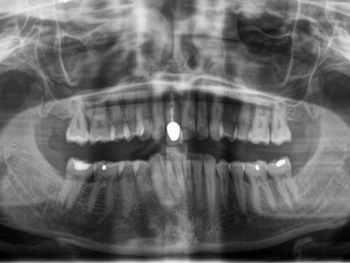

In diesem Fall hätte eine Brückenversorgung in regio 11 viel gesunde Zahnhartsubstanz gekostet. Daher fiel die Entscheidung der Patientin auf eine Implantatkrone. Neben des wiederholten Bruchs der Interimsprothese aufgrund des Tiefbisses stellte die provisorische Versorgung aufgrund der Lage im Frontzahnbereich hohe Anforderungen. Die Patientin verfügt überdies über eine hohe Lachlinie, bei der die Gingiva komplett sichtbar ist. Um den ästhetischen Ansprüchen gerecht zu werden, war eine gründliche Planung und längerer Vorlauf erforderlich. Das Ziel war nicht nur, ein ästhetisch befriedigendes Ergebnis zu liefern, sondern dieses auch langfristig zu erhalten. Deswegen dauerte die Vorbehandlung mit Socket Preservation, PA-Behandlung, Augmentation, Implantation und Gingivaformung durch die provisorische Krone insgesamt neun Monate.

Die Patientin zeigte sich mit dem Ergebnis jedenfalls hochzufrieden und lobte besonders die interdisziplinäre Zusammenarbeit zwischen behandelndem Zahnarzt Daniel Liss, Oberärztin Dr. Yun-Chie Roh, Chirurgin Dr. Irene Göllnitz und dem Zahntechniker Philip Janz.